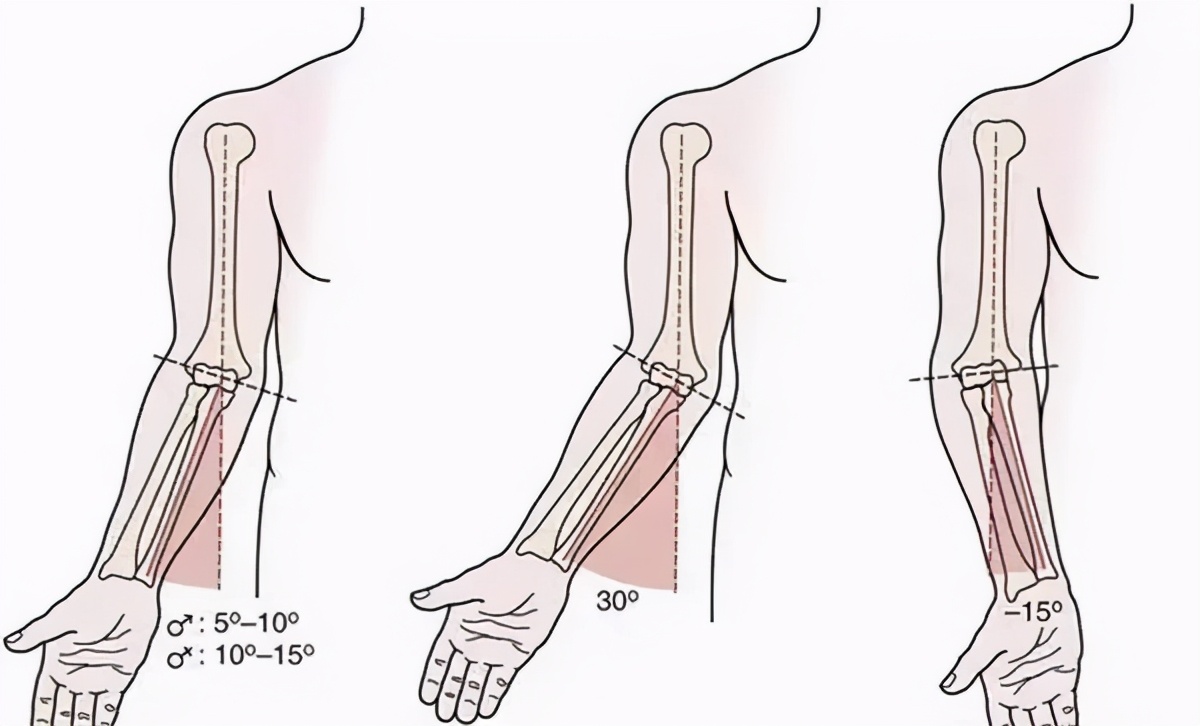

据欧阳元明介绍,正常人掌心向前,使肘关节保持自然伸直时,前臂轴线与上臂轴线,并不在一条直线上,而是会形成一定外翻角度,一般10~15度,称为“提携角”。

肘内翻时“提携角”丧失,并有一定内翻角度,肘内翻通常为肱骨髁上骨折后畸形愈合引起的,其多见于儿童。